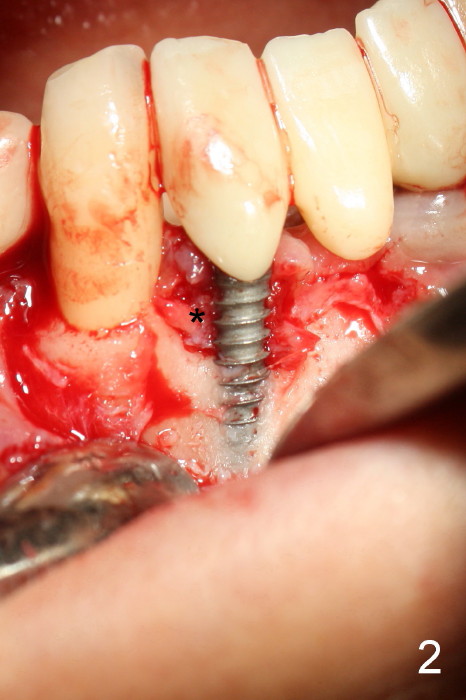

The patient has had chronic pain and swelling associated with the implant at the site of #26 (Fig.1). The extent of implant thread exposure is shown in Fig.2 after flap reflection; inflammatory granulation tissue is present around the most coronal threads (*, one year post cementation). Following debridement and Clindamycin soaking, allograft is placed around the exposed threads; a titanium mesh is used to contain the graft (Fig.3). The flap is closed with tension in spite of the periosteum being underscored. The patient develops moderate to severe ecchymosis postop.

The coronal portion of the mesh is exposed with loss of bone graft granules. It appears that the mesh has lost its function. It is planned to be removed. PA is taken 16 days post placement of the mesh (Fig.4).

Fig.5 is taken following local anesthesia to show the exposed mesh, 22 days post placement. When the latter is removed, the exposed threads appear to be less (Fig.6, as compared to Fig.2). There is healthy granulation tissue growth apically (*). The patient is asymptomatic 1 month post mesh removal; there is no tenderness around exposed threads (Fig.7). Connective tissue graft is planned to cover the exposed threads through tunnel technique. Thread exposure appears less 3 months post mesh removal (Fig.8). There is infection when the region is not kept clean (Fig.9 (2.5 years post mesh removal)). The other 1-piece implant should have minor implant exposure (<). It appears that there is no thread exposure associated with the immediate implant at #28. Using smaller 1-piece implants (2.5 or 2.0 vs. 3 mm) with flap surgery should be able to prevent the complication. The 72-year-old phobic patient declines any further treatment. Two years later, she agrees to have treatment because of repeated infection (Fig.10). Impression has been taken for stent. After sectioning FPD and removing the infected implant (Tatum), a smaller implant will be placed in between the implants. If her vein is not too small, blood will be drawn for PRF.